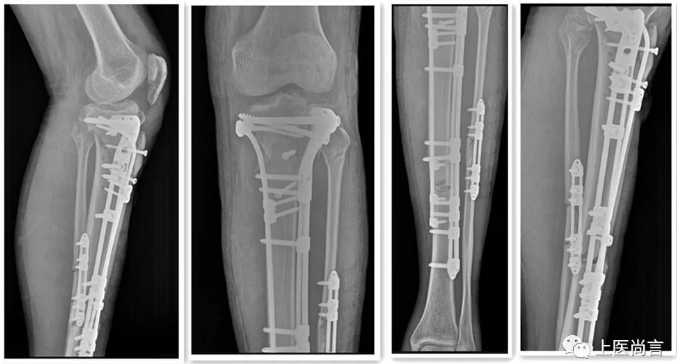

手术后DR片

经过充分的术前准备,在熊鹰教授的指导下成功为该患者进行左胫骨平台、胫腓骨下段骨折小切口切开复位桥接系统内固定术,由于术前采用了3D打印技术,治疗团队对患者骨折情况进行了全方位的掌握,并依据3D打印模型确定了手术方案,内固定物型号,手术时间大大缩短,减小手术创伤,减少手术出血,极大的减轻了患者痛苦和风险,手术顺利完成,术后张先生全身状况恢复良好,目前正在积极进行康复锻炼。